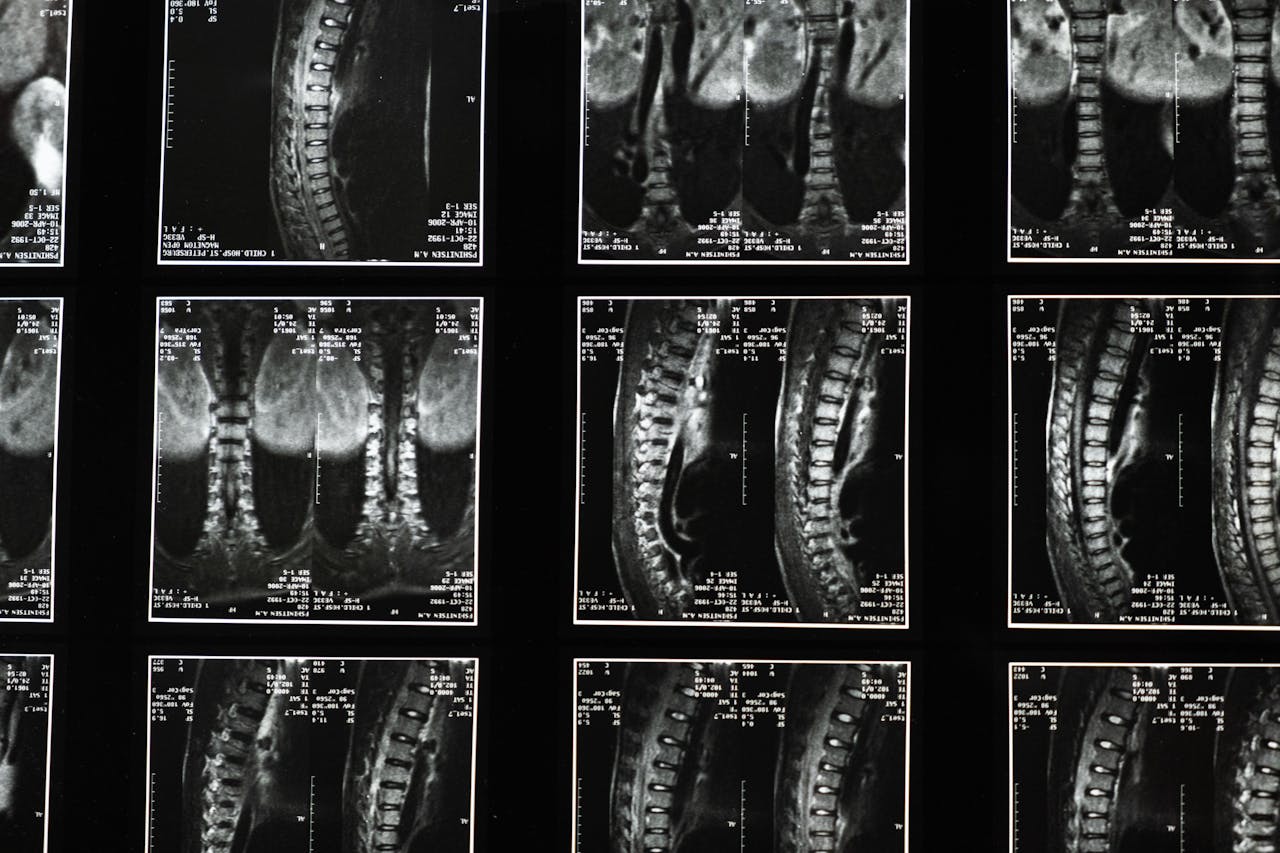

Spine Surgery

Specialized treatments for complex spinal conditions.